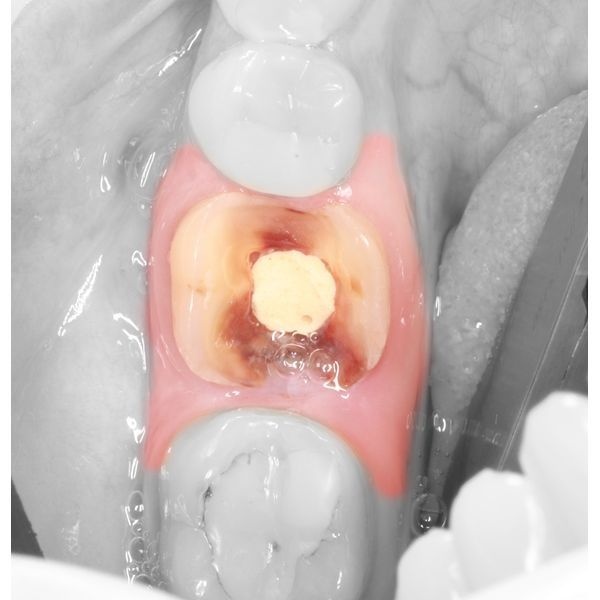

При осмотре индекс разрушения окклюзионной поверхности зуба (ИРОПЗ) правого нижнего моляра составил 1,0, т. е. жевательная поверхность зуба была полностью разрушена.

- зуб 4.6 разделили на мезиальную и дистальную части с помощью алмазного цилиндрического бора и фрезы Линдемана, чтобы облегчить удаление и сохранить корни;

- сегменты извлекли элеватором и щипцами, после чего можно было увидеть широкую межкорневую перегородку костной ткани невооружённым глазом;